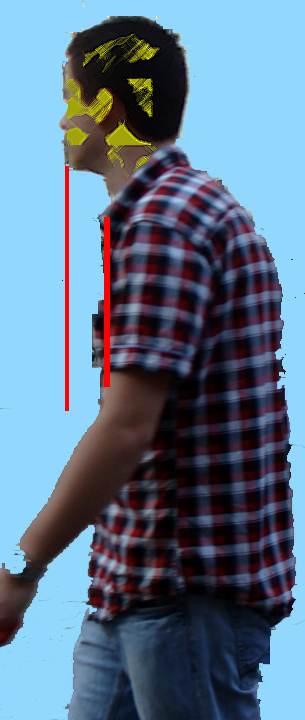

Ha a “JELLEMZŐ TÜNETEK” rovatban felsoroltak között szerepel olyan panasz amire ráismer, akkor egyszerű módon valószínűsítheti, hogy tényleg elmozdult helyzetben van-e az atlasza. Mivel szinte mindenkinél tapasztalható az atlasz valamilyen mértékű elfordulása vagy/és elbillenése, ezért az önteszttel annak súlyosságára és a már bekövetkezett károsodásra is következtethetünk. 1., Normál, álló helyzetű testartásunkkal nézzünk egy tükörbe. Figyeljük meg, hogy a fejünk és […]]]>

Ha a “JELLEMZŐ TÜNETEK” rovatban felsoroltak között szerepel olyan panasz amire ráismer, akkor egyszerű módon valószínűsítheti, hogy tényleg elmozdult helyzetben van-e az atlasza. Mivel szinte mindenkinél tapasztalható az atlasz valamilyen mértékű elfordulása vagy/és elbillenése, ezért az önteszttel annak súlyosságára és a már bekövetkezett károsodásra is következtethetünk. 1., Normál, álló helyzetű testartásunkkal nézzünk egy tükörbe. Figyeljük meg, hogy a fejünk és […]]]>